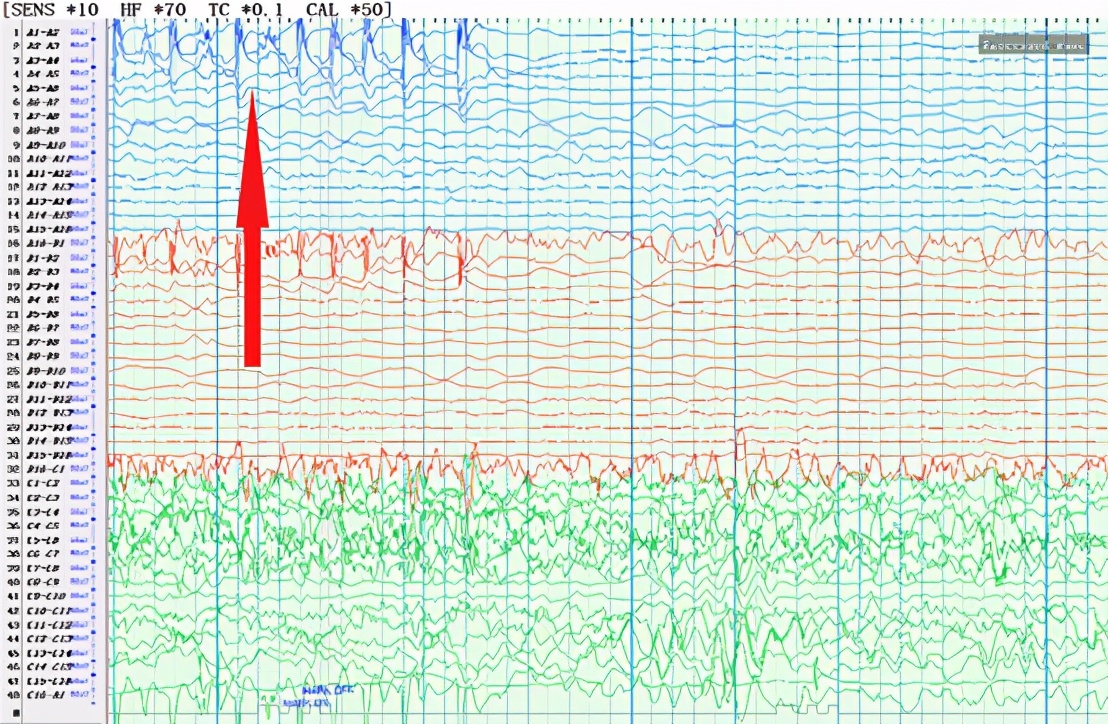

发作期脑电图:

红色箭头所指为癫痫发作时的异常波形